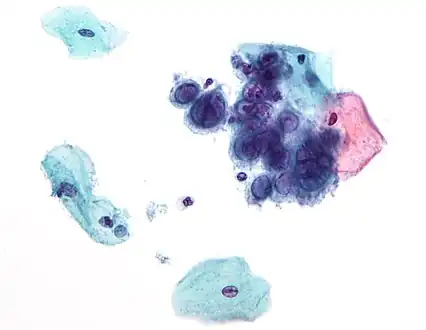

- The human papillomavirus (HPV) is the most common STI in the United States.[60] There are more than 40 different strands of HPV and many do not cause any health problems. In 90% of cases the body's immune system clears the infection naturally within 2 years.[61] Some cases may not be cleared and can lead to genital warts (bumps around the genitals that can be small or large, raised or flat, or shaped like cauliflower) or cervical cancer and other HPV related cancers. Symptoms might not show up until advanced stages. It is important for women to get pap smears in order to check for and treat cancers. There are also two vaccines available for women (Cervarix and Gardasil) that protect against the types of HPV that cause cervical cancer. HPV can be passed through genital-to-genital contact as well as during oral sex. It is important to remember that the infected partner might not have any symptoms.